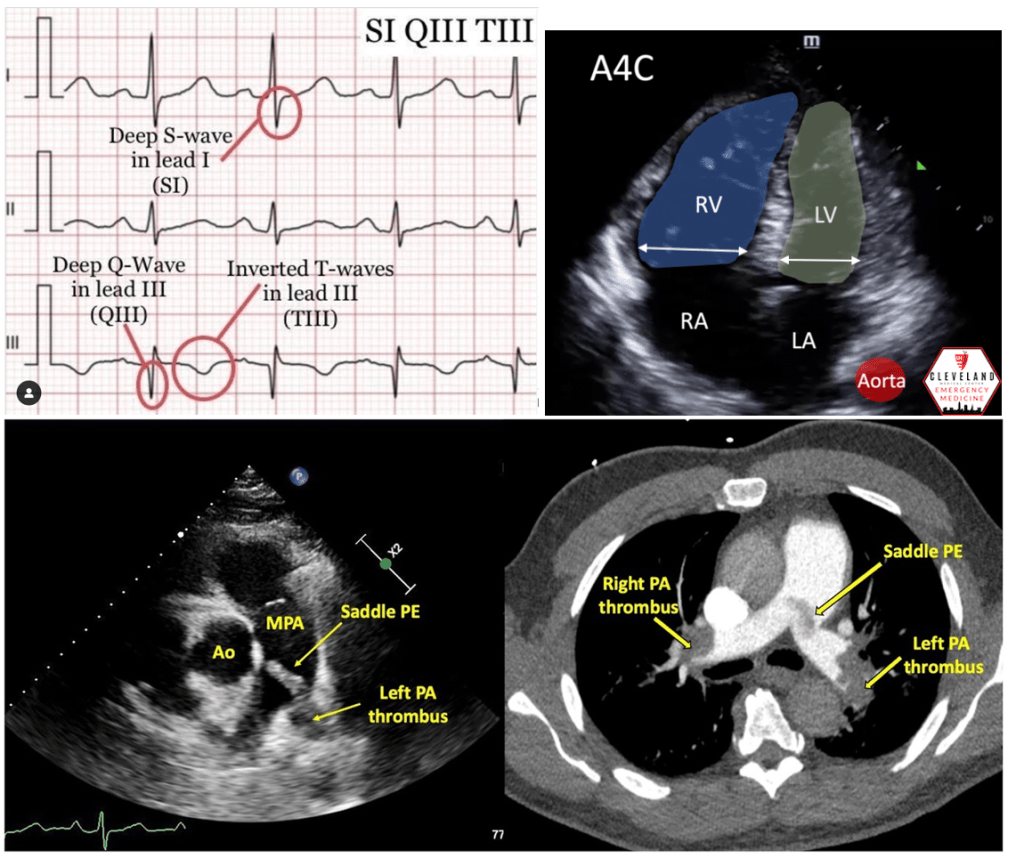

Answer: C) S1Q3T3 pattern on ECG

This 45-year-old man has a confirmed massive pulmonary embolism (PE) with clinical signs of right ventricular strain. The S1Q3T3 pattern on ECG is a hallmark finding associated with severe right ventricular strain caused by acute pressure overload.

• The S1Q3T3 pattern refers to the presence of a deep S wave in lead I, a Q wave in lead III, and an inverted T wave in lead III. This finding indicates right heart strain, commonly associated with massive or submassive PE.

• Right ventricular strain occurs when the right ventricle struggles to pump against the sudden increase in pulmonary artery pressure caused by the embolism.